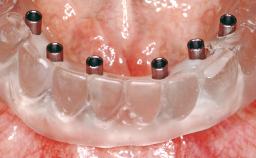

# of Implants 6

Type of Implants One-Piece

Modality 6+ implants with immediate loading